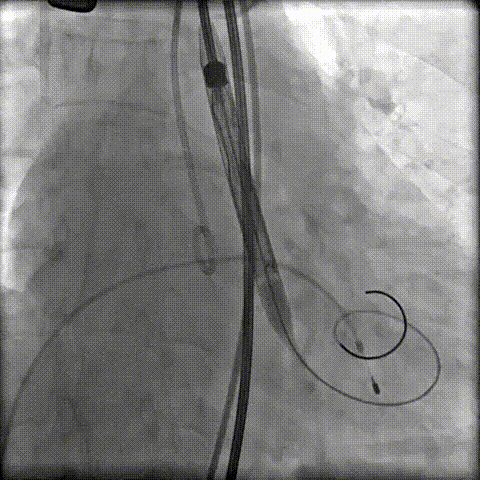

第二次定位释放

顺利脱钩撤鞘,瓣膜位置及形态理想,无明显瓣周漏